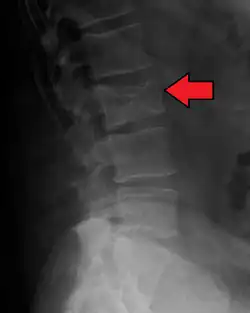

Medical imaging

The diagnostic examination of a person with suspected multiple myeloma typically includes a skeletal survey. This is a series of X-rays of the skull, axial skeleton, and proximal long bones. Myeloma activity sometimes appears as "lytic lesions" (with local disappearance of normal bone due to resorption) or as "punched-out lesions" on the skull X-ray ("raindrop skull"). Lesions may also be sclerotic, which is seen as radiodense.[76] Overall, the radiodensity of myeloma is between −30 and 120 Hounsfield units (HU).[77] Magnetic resonance imaging is more sensitive than simple X-rays in the detection of lytic lesions. An MRI may supersede a skeletal survey, especially when vertebral disease is suspected. Occasionally, a CT scan is performed to measure the size of soft-tissue plasmacytomas. Nuclear Medicine Bone scans are typically not of any additional value in the workup of people with myeloma (no new bone formation; lytic lesions not well visualized on nuclear bone scan).

Pathological fracture of the lumbar spine due to multiple myeloma -